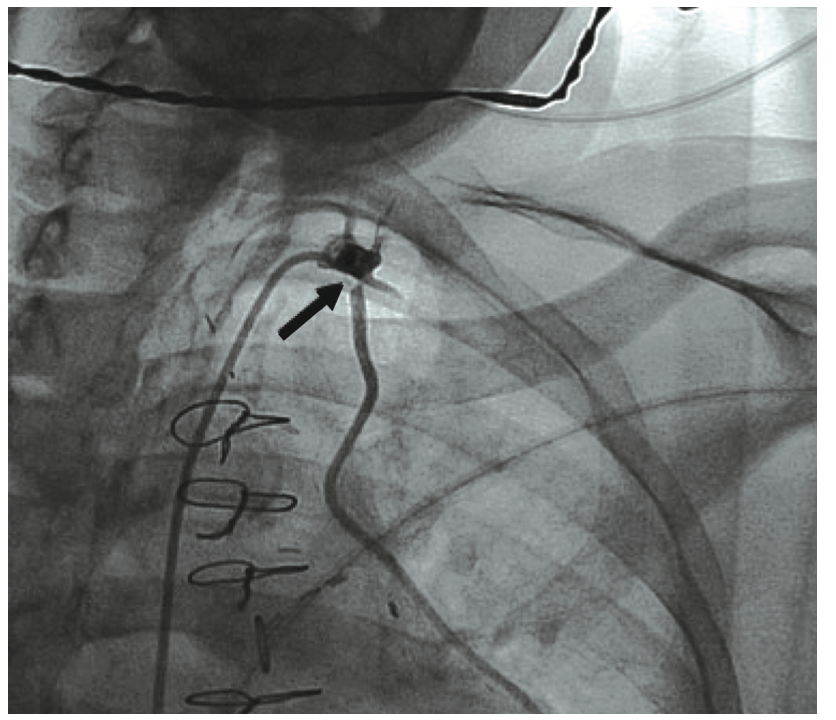

Given the patient’s complex anatomy with suboptimal hemodynamics, ad hoc percutaneous coronary intervention (PCI) was deferred in lieu of further heart team discussion and medical optimization. Her antiplatelet regimen was escalated from clopidogrel to ticagrelor, with a loading dose of 180 mg followed by 90 mg twice daily maintenance. She was scheduled for a series of extra hemodialysis/ultrafiltration sessions, leading to eventual percutaneous intervention several days later. Femoral access was employed in both diagnostic and intervention cases, given current and prior bilateral upper arm fistulas. Repeat pre-PCI LVEDP was improved at 23 mmHg. The LIMA to mid LAD ostial 75 to 80% stenosis with moderate to severe calcification was treated successfully with balloon angioplasty and intravascular lithotripsy (IVL) of a 3.5 mm x 12 mm C2 balloon (Shockwave Medical), using 50 pulses. IVL was followed by placement of a Xience Skypoint 3.5 mm x 12 mm drug-eluting stent (DES) (Abbott Vascular) that was post dilated to >3.75 mm at high pressure, resulting in 0% residual stenosis and normal blood flow grade 3 (TIMI [Thrombolysis in Myocardial Infarction]) (Figure 3A, Video 2).

Video 2. Coronary angiogram after successful Shockwave intravascular lithotripsy and stenting.